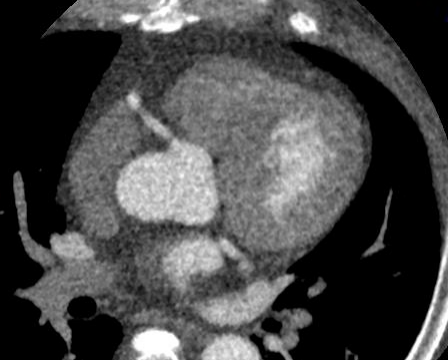

患者图像质量显示完美,

没有任何搏动伪影,血管显示清晰,

来吧,一起看图~

血管显示清晰,没有搏动伪影